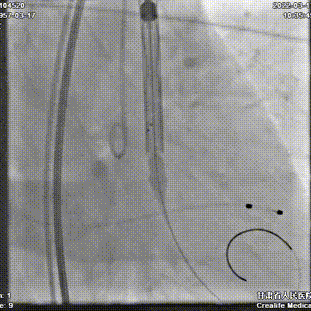

第一次定位释放

第一次释放后位置尚可

静待5分钟后位置明显下滑

回收调整超硬导丝后,再次定位

逐步释放瓣膜,工作位位置理想

工作位造影

瓣膜充分膨胀,完全释放

植入后位置理想,无反流